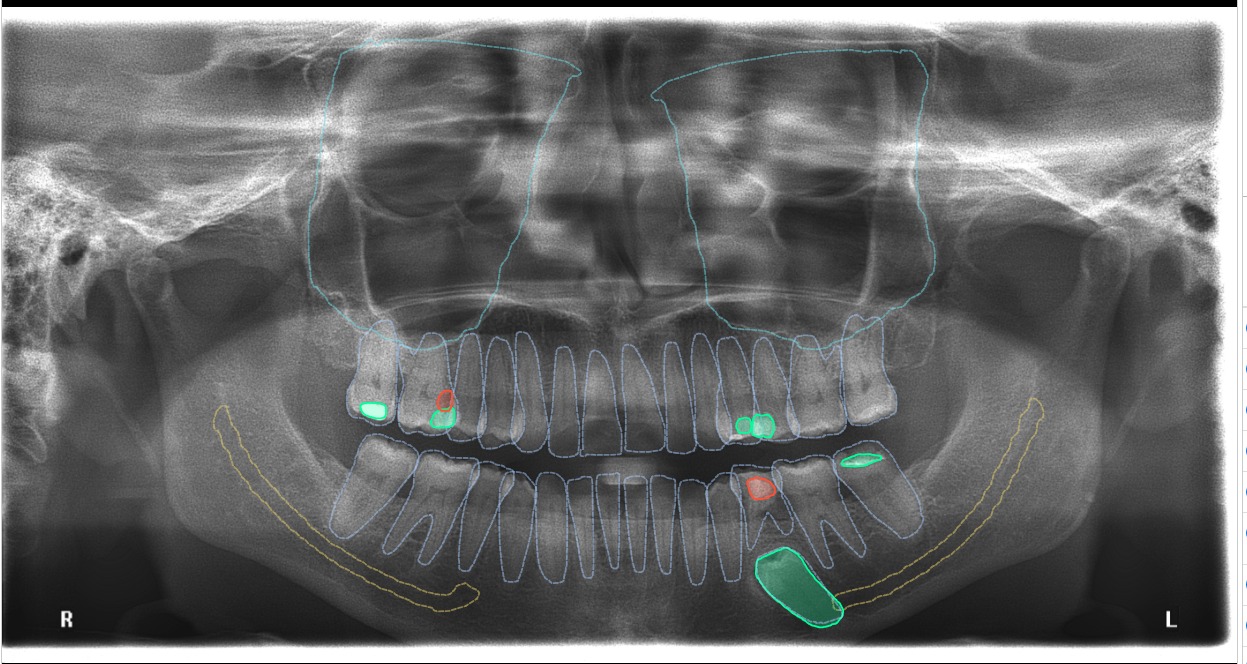

Orthopantomogram (OPG): A jaw-sized x-ray showing all teeth, upper and lower jaw bones, jaw joints, and maxillary sinuses.

- Our clinics are equipped with AI-guided solutions that can scan the OPG and detect abnormalities in approximately 5 seconds, helping dentists promptly diagnose oral conditions.

OPG Before AI-Guided Detection

OPG After AI-Guided Detection